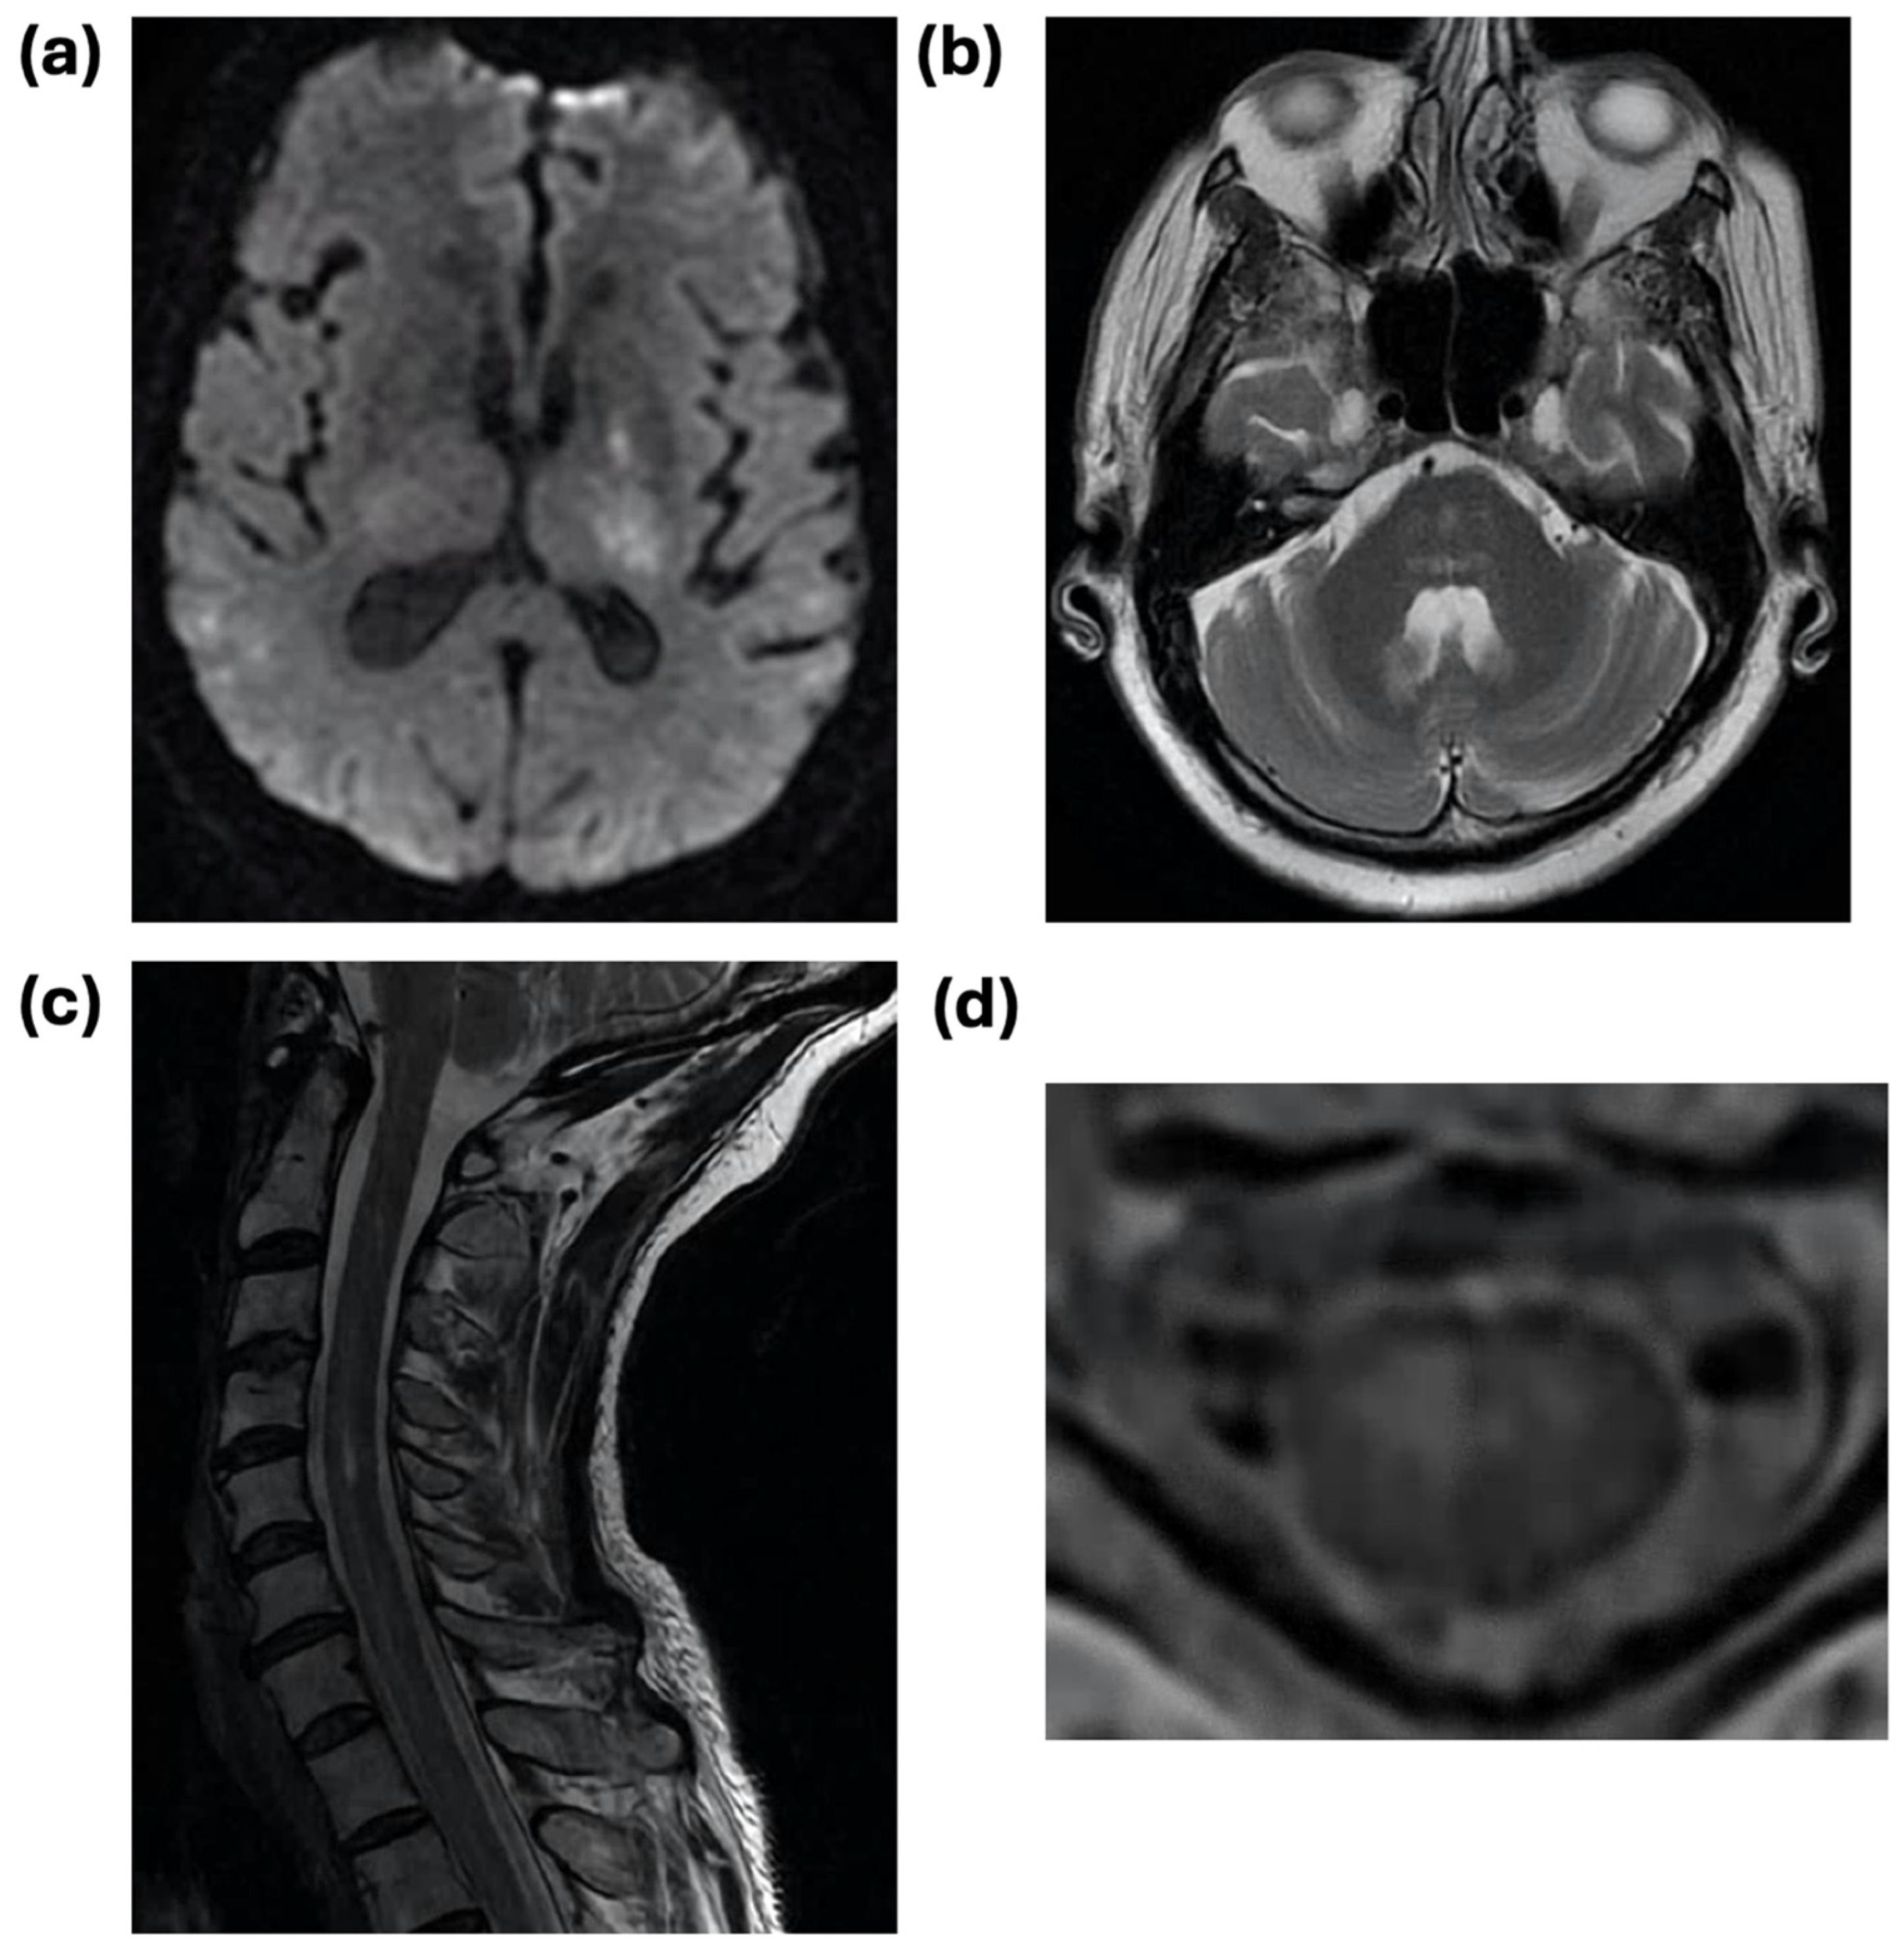

| Brain MRI performed | 29 (80.6%) | 22 (84.6%) | 3 (75.0%) | 4 (66.7%) |

| Any acute abnormality | 14 (48.3%) | 12 (54.6%) | 0 (0.0%) | 2 (50.0%) |

| Spine MRI performed | 13 (36.1%) | 8 (30.8%) | - | 5 (83.3%) |

| Any acute abnormality | 7 (53.9%) | 2 (25.0%) | - | 5 (100%) |